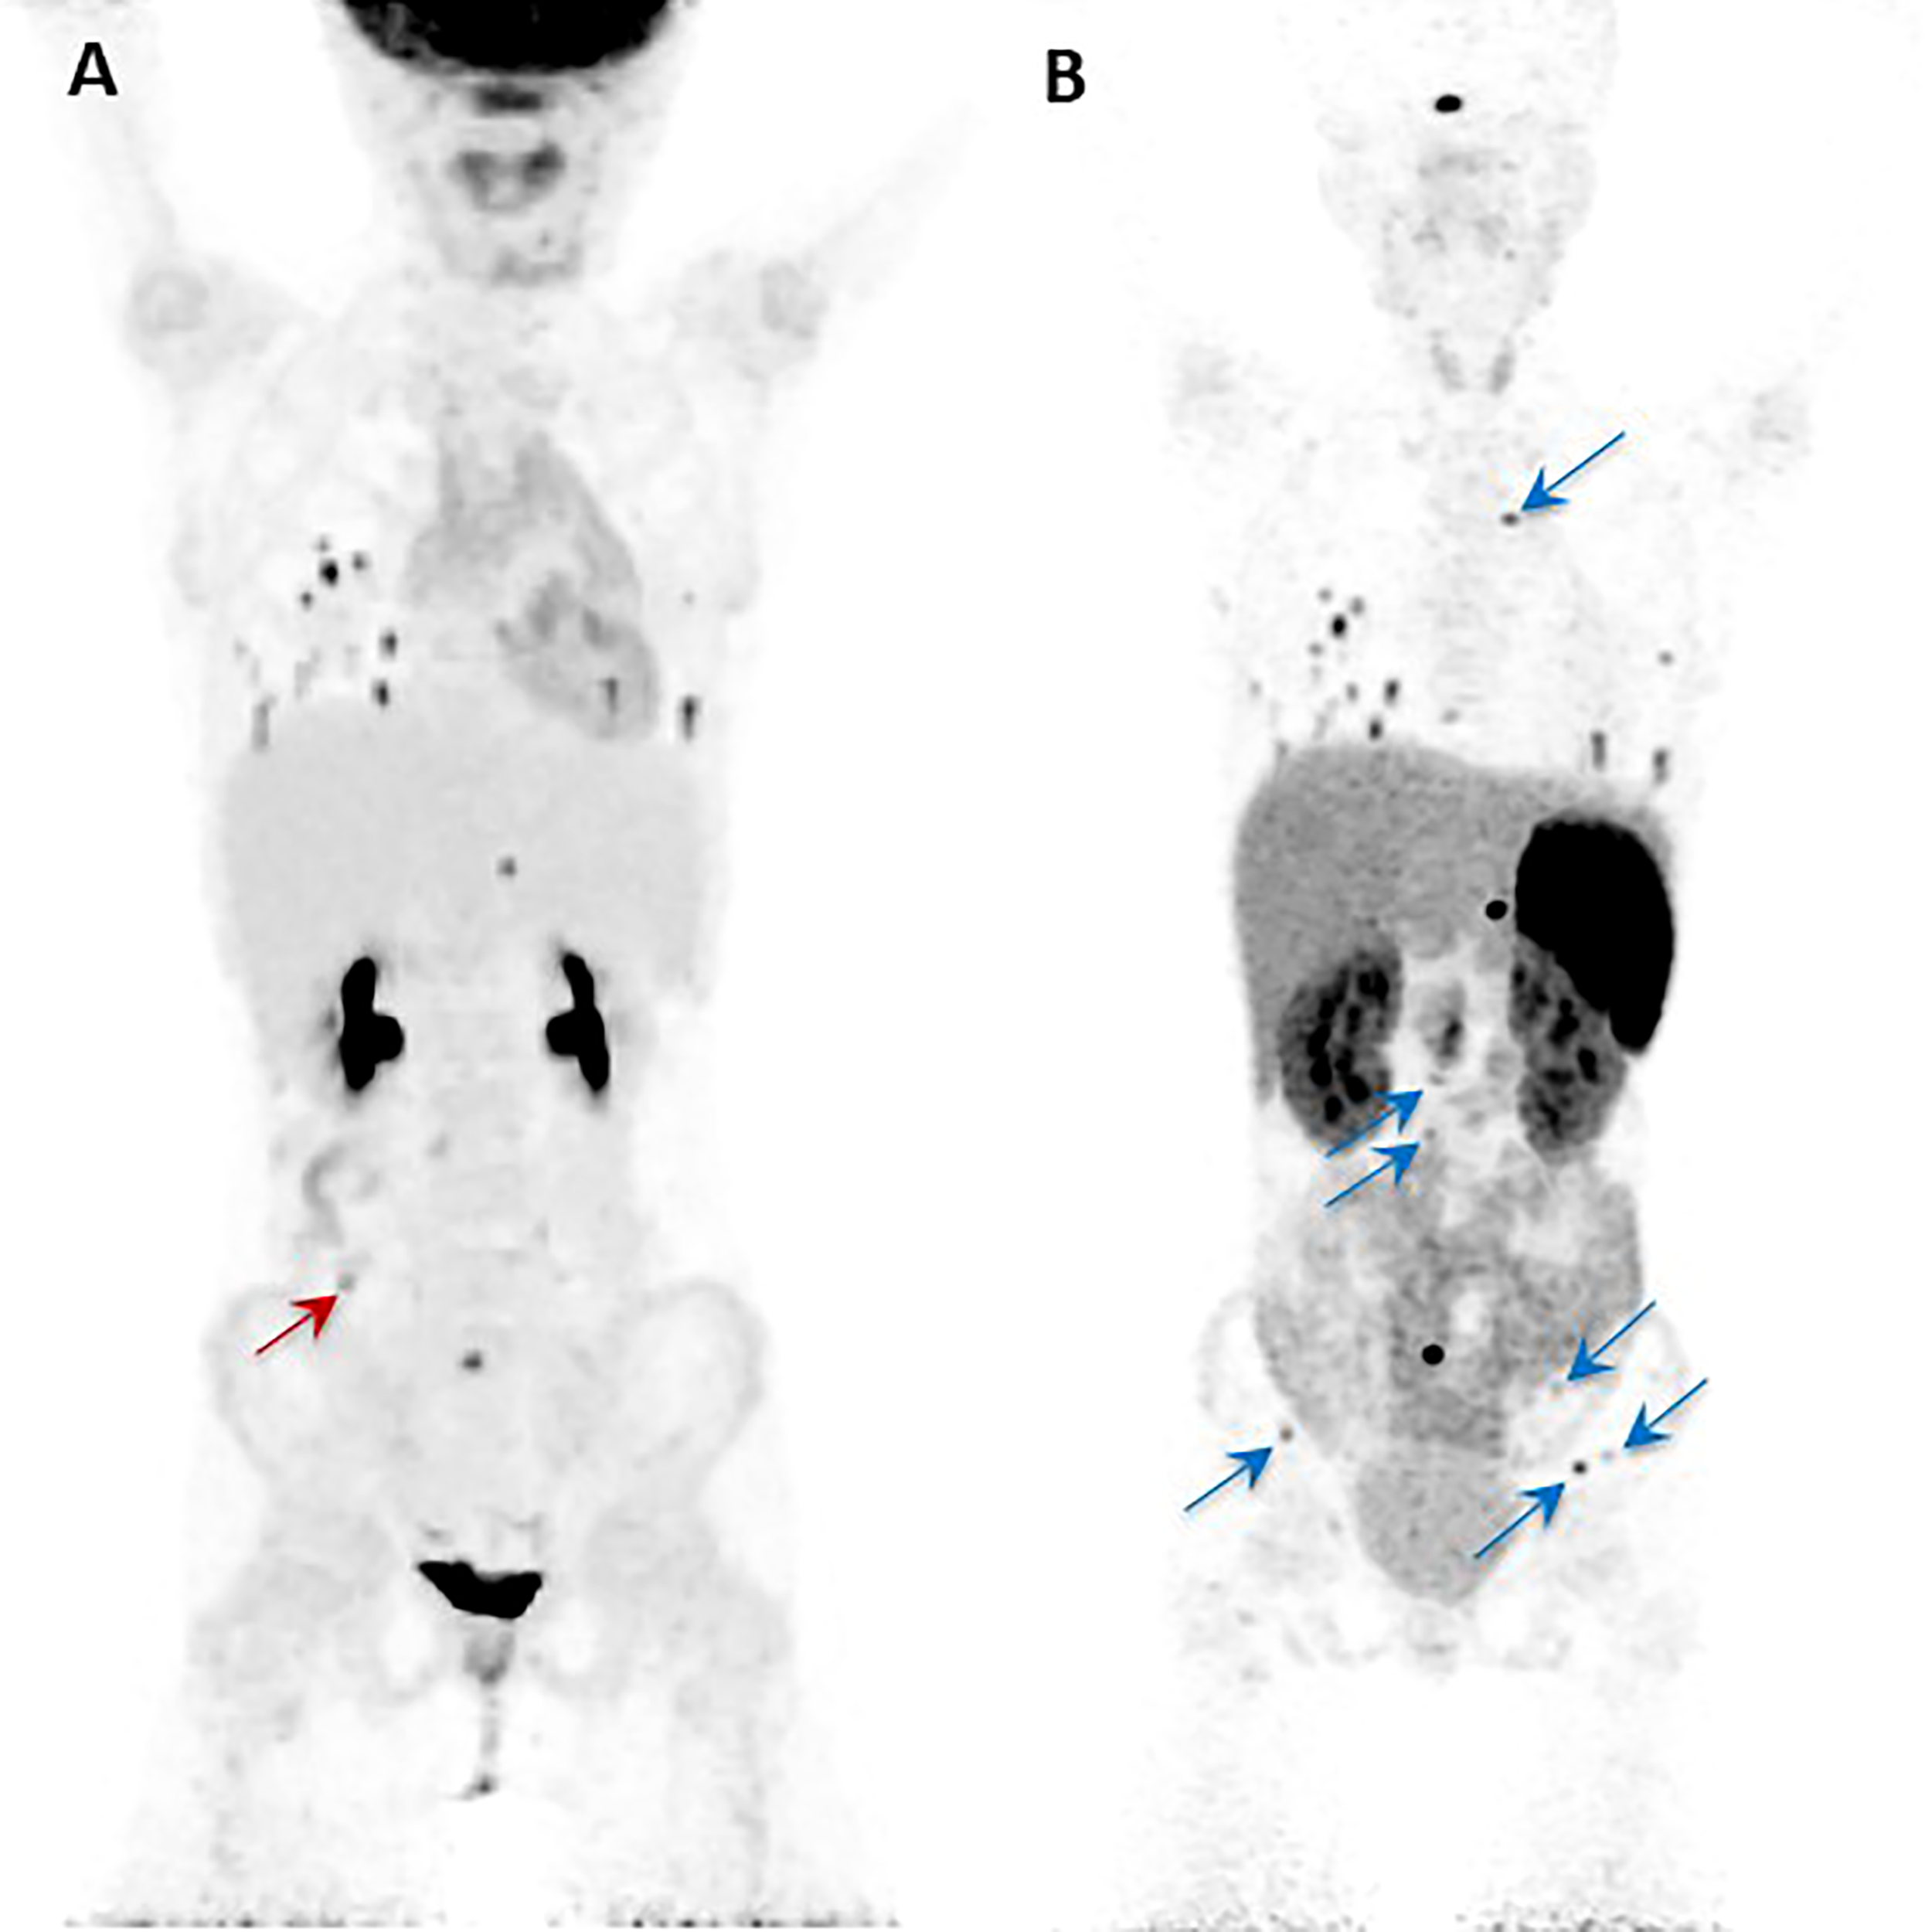

The other relevant application of the theranostic paradigm is for tumors expressing somatostatin receptors – especially type 2 (SSTR2) – that bind to somatostatin analogs (SSAs) linked to a chelator (DOTA) for the radionuclide. Typically, 68Ga- or 64Cu-DOTA-SSA is used for imaging, and 90Y- and 177Lu-DOTA-SSAs deliver the radiation dose to the sites of tumors, with the latter referred to as peptide receptor radionuclide therapy (PRRT) (42, 69). 68Ga-DOTATATE is commonly used since DOTATATE binds preferentially to SSTR2 over other somatostatin receptors, as opposed to DOTATOC or DOTANOC (42). 68Ga-DOTATATE is particularly useful for cluster 1A mutations (especially SDHx), HNPGLs, metastatic PPGL, and pediatric PPGL (42). Among nine pediatric patients with SDHx mutations, both 18F-FDG and 68Ga-DOTATATE detected lesions in all of the patients but 68Ga-DOTATATE had superior sensitivity on a per-lesion basis (94% compared to 79% on 18F-FDG) and was also more sensitive than anatomic imaging by CT or MRI with contrast enhancement (74%). 68Ga-DOTATATE was especially superior to CT/MRI for mediastinal lesion detection and superior to 18F-FDG for detection of adrenal and liver lesions, though 18F-FDG and CT/MRI outperformed 68Ga-DOTATATE for detection of other abdominal lesions (Figure 2) (70). These data offer a compelling case for performing 68Ga-DOTATATE PET/CT or 68Ga-DOTATATE PET/MRI with contrast enhancement to detect such abdominal lesions. Currently both functional and anatomic imaging are required for staging and for assessing treatment response in pediatric metastatic PPGL patients and, therefore, simultaneous PET/MRI may be considered in this cohort due to decreased radiation exposure, fewer instances requiring sedation or general anesthesia, fewer appointments, and simultaneous imaging with two advanced diagnostic imaging techniques (whole-body PET and MRI) (71). Recommended imaging modalities for different types of PPGL based on genetic and clinical features are summarized in Table 3. A 2015 meta-analysis by Han et al. pooled patients of unknown genetic background, finding a significantly superior detection rate of 68Ga-DOTA-conjugated somatostatin receptor-targeting peptide (68Ga-DOTA-SST) PET (93%) as compared to other functional imaging modalities (72). Therefore, in cases where a genetic etiology is not known, 68Ga-DOTATATE PET may be performed.

Figure 2

Anterior maximal intensity projection (MIP) images of the 18F-FDG PET/CT (A) and 68Ga-DOTATATE PET/CT (B) studies of a 10-year-old SDHB positive girl. She was diagnosed initially with metastatic disease at the age of 8 years. Her right paraaortic, retroperitoneal primary paraganglioma was surgically resected. On presentation to our institution, the progression of her disease was demonstrated by metastatic lesions in bone, lungs, and abdomen as shown in the images (A, B). The single red arrow on image (A) indicates the one lesion (abutting bowel) localized by 18F-FDG PET/CT that is not visualized by the 68Ga-DOTATATE PET/CT. Similarly, all the additional lesions (transverse process of T4 spine, L2-L5 vertebral bodies, left ilium, and left and right iliac wings) localized by the 68Ga-DOTATATE PET/CT (blue arrows) are not visualized by 18F-FDG PET/CT (B). This figure was adapted from the figure that was initially published as Figure 2 by Jha et al. (70).